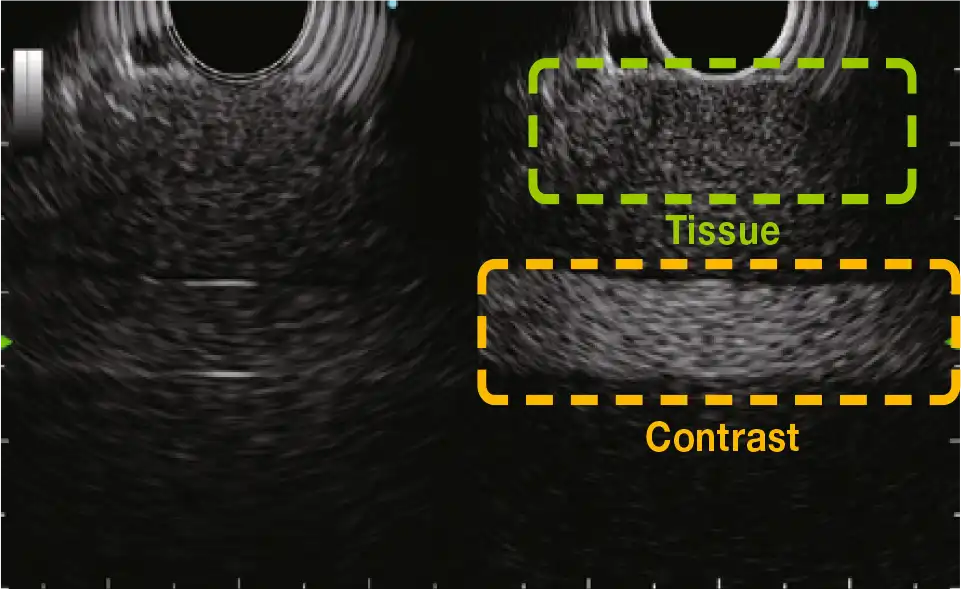

对比谐波超声 (CHE)

对比度谐波回声(CHE)对来自超声造影剂的谐波成分进行成像。

新增加的C-THE模式对生物组织的信号和对比度进行成像。